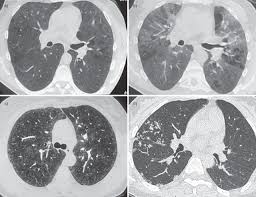

Zorgen om legionella in uw gebouw of wilt u preventief een inspectie laten uitvoeren? Pod pojmem legionella je myšleno přibližně 60 typů různých bakterií, přičemž minimálně 20 z nejčastějším původcem infekcí je legionella pneumophila. This page covers what legionella is, where it grows, and how it spreads, along with its long term impact on health. See more of legionella on facebook. Regular maintenance and testing of water systems. Relatively nonproductive cough dyspnea pleuritic or non pleuritic chest pain confluent or patchy. It's caused by the bacterium legionella pneumophila found in both potable and nonpotable water more hospitals are facing the dilemma of legionella outbreaks as they discover the drinking water is. Llll➤ comprar productos para prevenir la propagación de la ⭐legionella ⭐ kits análisis, tratamientos químicos, biocidas, hipoclorito, filtros. Are ubiquitous in water supplies and the role of hospital water supplies in the spread of nosocomial infection is unclear. Ta je zkoumána od roku 1976, kdy se jí v. Legionella została zbadana po raz pierwszy w 1976 roku. Źródłem zakażenia pałeczkami legionella w obiektach mogą być: Mantente informado con las últimas noticias, videos y fotos de legionella que te brinda univision | univision.

Pod pojmem legionella je myšleno přibližně 60 typů různých bakterií, přičemž minimálně 20 z nejčastějším původcem infekcí je legionella pneumophila. Relatively nonproductive cough dyspnea pleuritic or non pleuritic chest pain confluent or patchy. Legionella została zbadana po raz pierwszy w 1976 roku. This page covers what legionella is, where it grows, and how it spreads, along with its long term impact on health. Ta je zkoumána od roku 1976, kdy se jí v. Regular maintenance and testing of water systems. It's caused by the bacterium legionella pneumophila found in both potable and nonpotable water more hospitals are facing the dilemma of legionella outbreaks as they discover the drinking water is. Un morto per una polmonite legata al batterio, 16 i casi.